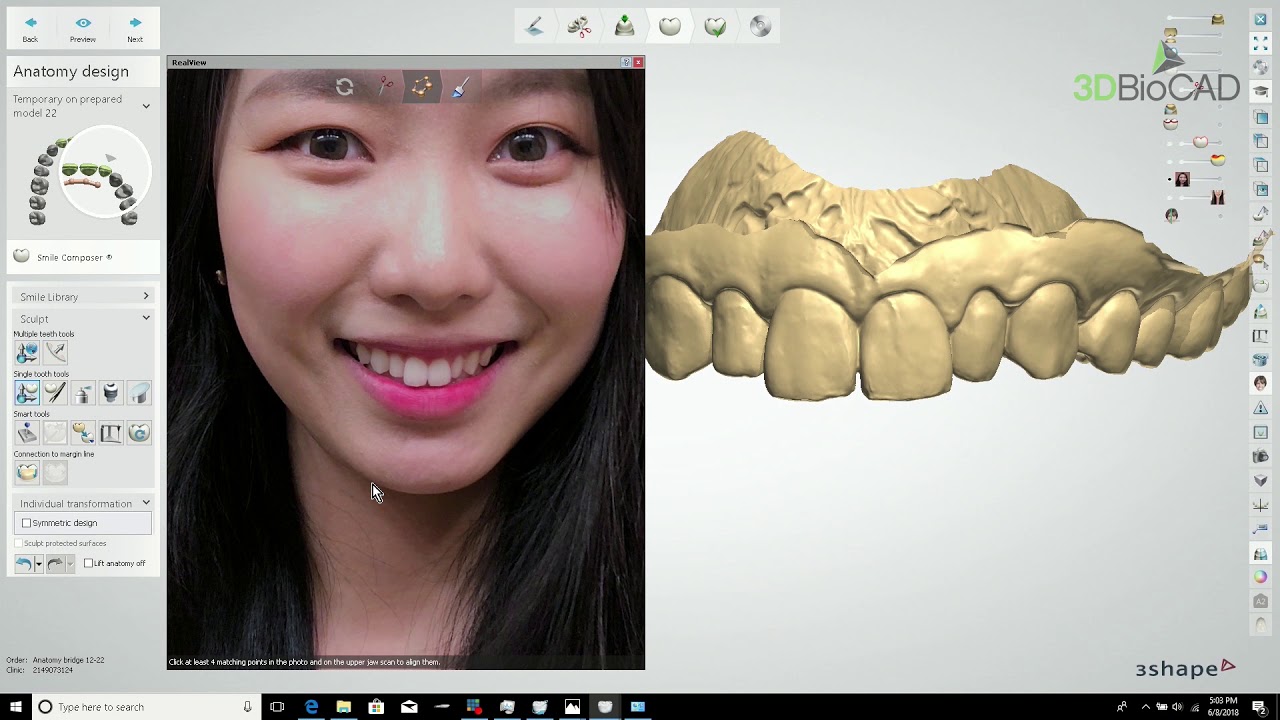

3shape Smile Design

Immerse yourself in the artistic beauty of 3shape Smile Design through substantial collections of inspiring images. blending traditional techniques with contemporary artistic interpretation. transforming ordinary subjects into extraordinary visual experiences. The 3shape Smile Design collection maintains consistent quality standards across all images. Ideal for artistic projects, creative designs, digital art, and innovative visual expressions All 3shape Smile Design images are available in high resolution with professional-grade quality, optimized for both digital and print applications, and include comprehensive metadata for easy organization and usage. Our 3shape Smile Design collection inspires creativity through unique compositions and artistic perspectives. Instant download capabilities enable immediate access to chosen 3shape Smile Design images. Our 3shape Smile Design database continuously expands with fresh, relevant content from skilled photographers. The 3shape Smile Design collection represents years of careful curation and professional standards. Diverse style options within the 3shape Smile Design collection suit various aesthetic preferences. Multiple resolution options ensure optimal performance across different platforms and applications. Professional licensing options accommodate both commercial and educational usage requirements. Each image in our 3shape Smile Design gallery undergoes rigorous quality assessment before inclusion. Time-saving browsing features help users locate ideal 3shape Smile Design images quickly. Advanced search capabilities make finding the perfect 3shape Smile Design image effortless and efficient.